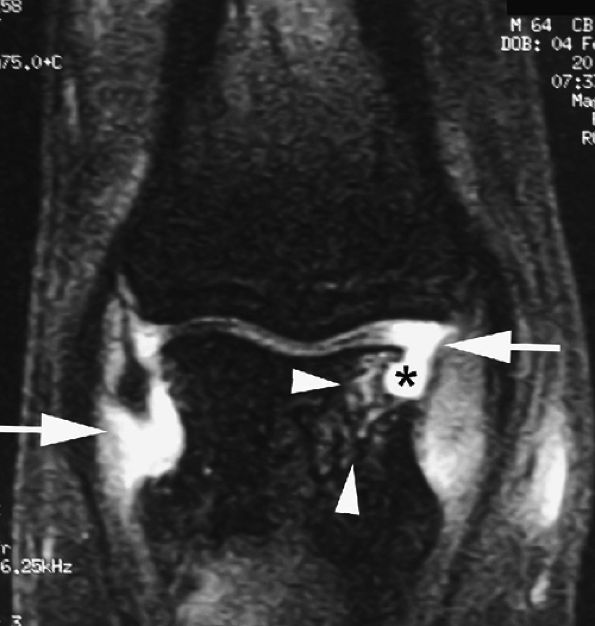

FIGURE 11.20 ● Acute injury of the radial collateral ligament (RCL) of the PIP joint of the fourth finger. Coronal (A) and axial (B) post-contrast fat-suppressed T1-weighted images displaying distal avulsion of the RCL with a proximal retraction (black arrows). The retinacular apparatus is displaced (arrowheads) with periligamentous edema. The ulnar collateral ligament is also identified (white arrows).